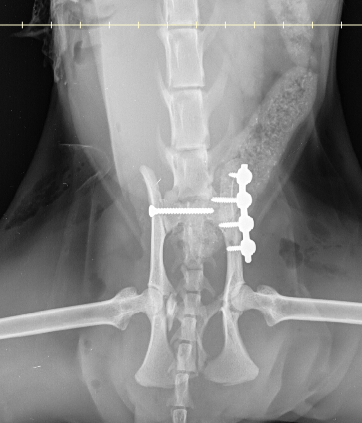

To address her injuries, a 2.4mm screw was placed to stabilize the sacroiliac joint, and a 2mm SOP plate with two proximal and two distal screws was used to reduce the ilial fracture (Figs. 3 and 4).

Fig. 3

Fig. 4